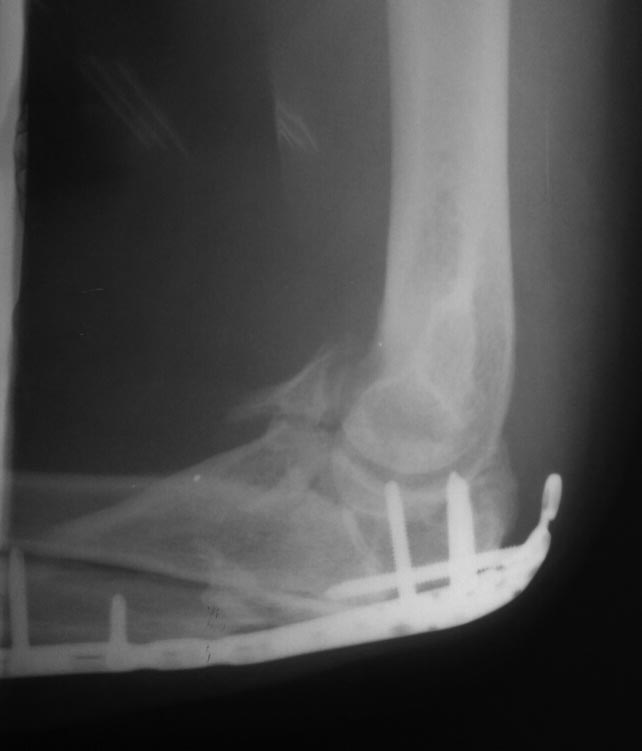

Консолидированный перелом проксимального отдела локтевой кости в

условиях накостного остеосинтеза. Сросшийся перелом венечного отростка

от февраля 2015.

Поступил к нам в учреждение спустя 4 месяца с момента оперативного

лечения. Жалобы на ограничение движения в суставе, разгибание до

140-145., сгибание до 100-105. Сустав отечный, пальпация незначительно

болезненная. При пассивных движениях определяется патологический хруст в

суставе.Выполнено оперативное лечение - удаление  металлоконструкции.

Остеотомия локтевого отростка. При ревизии сустава - винт в суставе,в

локтевой ямке отверстие от винта, имеется повреждение блока в виде

дефекта хрящевой ткани полосами, перелом верхнего полюса головки лучевой

кости(отломок 1\3 диаметра головки в полости сустава). В суставе

выраженный спаечный процесс. Выполнено удаление рубцовой

ткани, удаление отломка головки лучевой кости. Отмечается консолидация

венечного отростка,между отломков около 0.8 см рубцовые ткани. Выделение

венечного отростка, рубцовые ткани удалены. Остеосинтез венечного

отростка двумя винтами "типа Герберта". Интраоперационно разгибание 180,

сгибание 125-130. Хотелось узнать ваше мнение